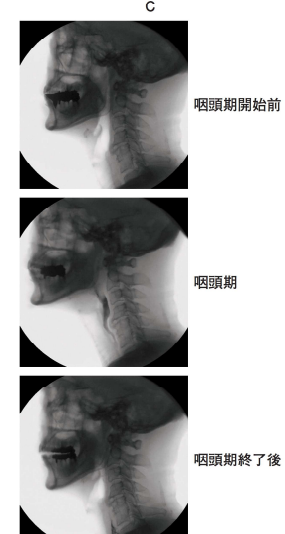

76 歳の女性。口や鼻から飲み物が漏れることを主訴として脳神経内科からの紹介で来院した。 1 年前に脳梗塞の診断を受けている。現在普通食を 20 分以内で全量摂取しており、咀嚼時の疲労感はなく、むせることはないが、飲水時に口や鼻から漏れることがあるという。口腔機能時の顔面写真(別冊No. 11A)、口腔機能時の口腔内写真(別冊No. 11B)及び液体の嚥下を記録した嚥下造影検査画像(別冊

No. 11C)を別に示す。

C:嚥下造影検査では誤嚥は認められない

真ん中の写真:飲み込めているけれど左側に食べ物が偏っていることがわかる。

最後の写真:右側で止まっている。⇒右側飲み込めていない⇒飲み込みづらいと感じる原因

aの頸部回旋:首を回した反対側の梨状窩が通過しやすくなる。⇒食道の入口が開きやすくなる⇒ひっかかるのを防止できる。